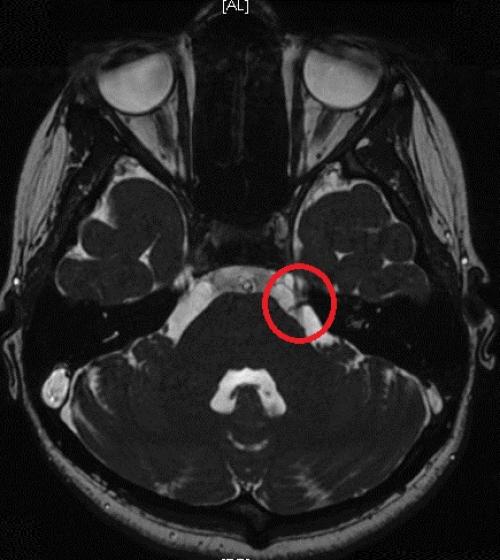

зуба, кружком обведен | Стреляющая боль во всех трех ветвях была следствием плохого кровообращения в мозговых отделах тройничного нерва у пожилой женщины. Кружком обведен участок мозга, пострадавший от закупорки одного из сосудов головного мозга. Проверить сосуды головы и шеи | Невралгия тройничного нерва была у молодой женщины из-за давления одной из мозговых артерий на корешок тройничного нерва. На МР-томограмме видно пересечение тройничного нерва (идет вертикально) с артерией (идет горизонтально). Артерия оказывала давление на тройничный нерв в месте его выхода из ствола мозга. |

- Сдавливание (компрессия) . Происходит, когда на нерв оказывается давление извне. Часто причиной явления служит контакт кровеносного сосуда (артерии или вены) с корешком тройничного нерва. Реже такое случается при опухолях, кистах или других образованиях.